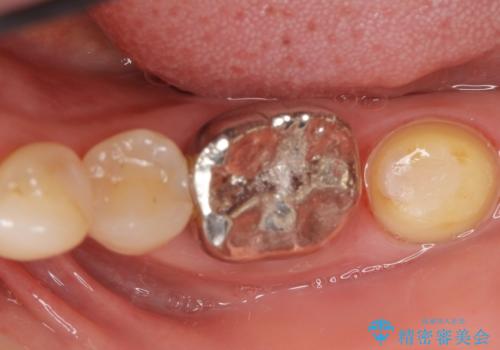

左下の奥歯(左下7)は破折しており保存不可能な状態でした。

ご希望により、隣の親知らず(左下8)を移植しました。

移植後、生着を待って根管治療及び補綴修復を行いました。